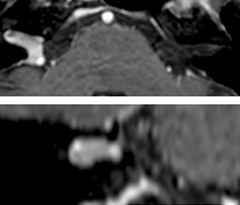

Giant cell arteritis

The 3D TSE T1w black blood MSDE sequence with fat suppression has an isotropic 0.8 mm voxel size and sagittal oblique and axial reformats are made. The images show superficial temporal artery thickening and peri-arterial fat infiltration. The 3D TSE PDw black blood MSDE with fat suppression has 0.55 mm isotropic voxels. The images shows focal involvement of the frontal branch of the superficial temporal artery.